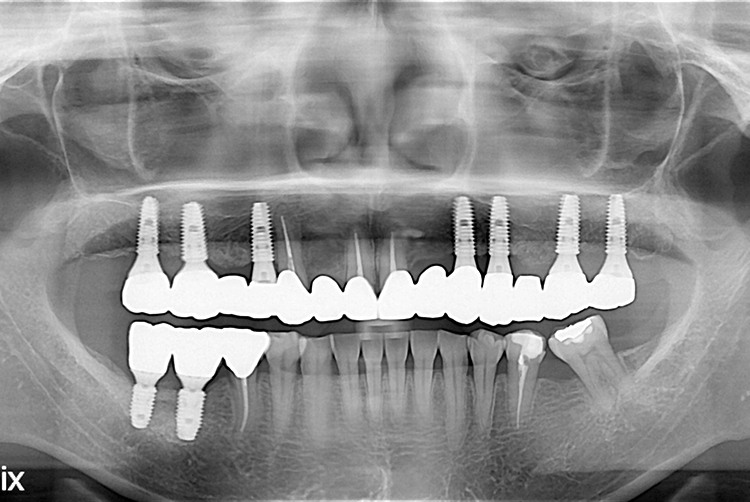

[임플란트] 임플란트

치료전 : 2018-08-22

21.03.17.jpg

치료후 : 2021-03-17

세종치과는 많은 환자와 다양한 케이스를 바탕으로 항상 편안한 임플란트 수술을 제공하고자 노력하고,

오래동안 튼튼히 쓸 수 있는 임플란트 수술을 가장 큰 목표로 삼고 있습니다